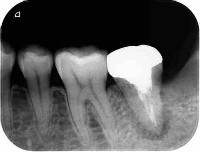

しっかりと感染歯質をとり、緊密に最終的なお薬をつめているので歯とお薬のコントラストもはっきりしています。

根の治療をした後は穴を埋めなければなりません。その材料として

1:金属

2:樹脂

の二つあります。その時の根の状態により、より良い方法で製作します。